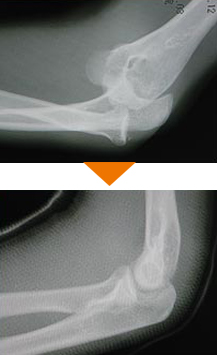

スポーツ外傷

スポーツ外傷、交通外傷、労働災害、家庭や職場による一般外傷などは認定医が適切な診断、診察を行います。